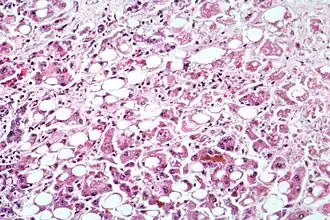

| Doença hepática alcoólica evidente por transformação gordurosa, morte celular e corpos de Mallory | |